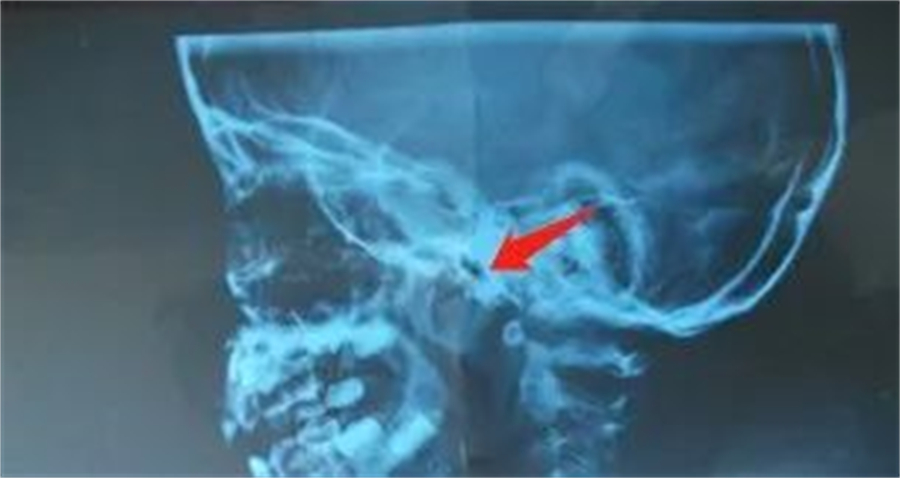

鼻咽侧位片的腺样体肥大

对此,她表示,腺样体位于鼻咽部后壁及顶部,腺样体炎症反复发作或鼻腔、鼻窦、扁桃体等腺样体邻近部位出现炎症,波及鼻咽部、反复刺激腺样体,可导致腺样体肥大。腺样体肥大常伴有扁桃体肥大、过敏性鼻炎、鼻窦炎,会出现鼻塞、喷嚏、咳嗽、张口呼吸、夜间睡眠不安、夜间打鼾等临床表现,如果压迫咽鼓管或者继发咽鼓管功能障碍,会导致分泌性中耳炎,造成儿童听力下降,影响生活。